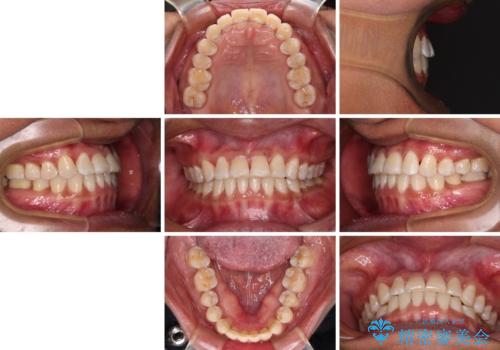

反対咬合の改善 途中で出産をしながらワイヤー矯正

- 治療期間

- 2年

咬合力が強く、反対咬合の改善に時間がかかりましたが、その後はスムーズに進めることができました。

途中、妊娠と出産があり、治療が中断したため、治療期間は延びましたが、出産も矯正治療も無事に終えることができました。